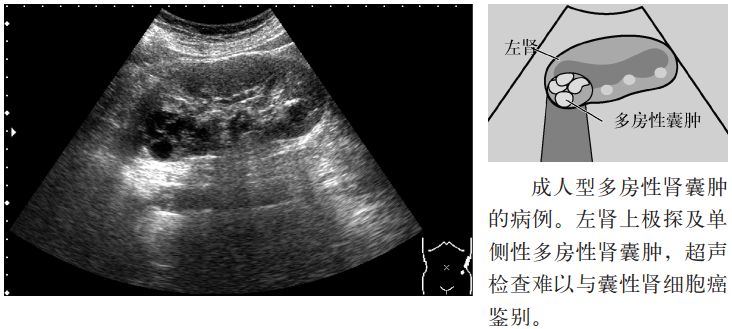

6.较大的多房性肾囊肿(multilocular cyst),需要与囊性肾细胞癌鉴别。通常是单侧性孤立性肿瘤,大多数间隔内不含肾单位,而含有不成熟的组织,被称为多房囊性肾细胞瘤(multilocular cystic nephroma,MLCN),其归属于肾母细胞瘤,较为罕见。多发生于4~20岁或40岁以后两个年龄段,幼儿多为男性,成人多见于女性。在幼儿,常伴有肾母细胞瘤成分,因此又称为部分分化型囊性肾母细胞瘤(cystic partially differentiated nephroblastoma,CPDN)。另外,应注意也有合并肾细胞癌或Wilms瘤的情况。

图7 多房性肾囊肿